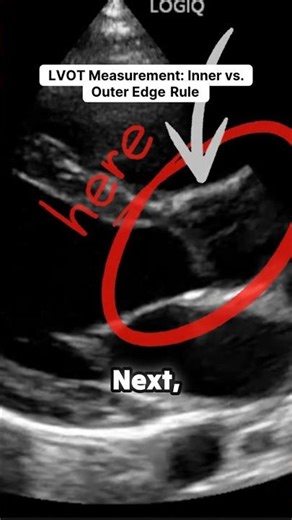

Normal LVOT Measurement in Echo 的热门建议 |

- LVOT Measurement Echo

LVOT Measurement - Ava

Measurement Echo - LVOT